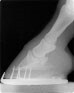

You will note that not infrequently, the so-called “high” heel is actually of a very acceptable height and the limb shows a good pastern axis and hoof angle. Radiographs of this foot may be very acceptable. In this case, the low heel is likely under-run to some degree and exhibits a long toe with flare present.

Structures of the foot must have proper form and spatial arrangement to function properly. Many feet develop low heels and a longer toe. This puts the foot out of balance, the coffin joint is placed more towards the back of the foot, increasing load on the heel region and creating a lengthy toe lever, putting more strain on the deep digital flexor tendon and potentially contributing to or exaggerating a toe first landing.